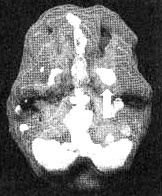

Мозг Марка — посттравматический стресс и головные боли

Трехмерное изображение — активный мозг, вид снизу. Обратите внимание на повышенную активность базальных ганглиев слева (помечено стрелкой).

Результаты вышли за рамки нормы. Мы обнаружили значительно повышенную активность базальных ганглиев в левой части мозга. Такой гиперактивности в этой области мне прежде видеть не доводилось. Левосторонние нарушения функций базальных ганглиев часто встречаются у людей, которые постоянно находятся в раздраженном или гневном состоянии. В этих случаях помогают препараты, стабилизирующие настроение, — такие, как литий, Tegretol или Depakote, снижающие раздражительность и помогающие успокоить «разогретые» участки в головном мозге. Марку я назначил Depakote. Почти сразу прекратились головные боли, а сам он стал спокойнее. Он прекратил «кидаться» на окружающих и стал способен заняться своим психологическим выздоровлением после развода и травм, полученных во Вьетнаме.

Во время работы с Марком у меня сложилось впечатление, что пребывание во Вьетнаме перепрограммировало его базальные ганглии на постоянную работу в режиме «начеку». На протяжении всех 13 месяцев, которые он провел на войне, каждый день он должен был оставаться «начеку», чтобы его не убили. Все последующие годы у него не было возможности перепрограммировать свой мозг для работы в нормальном режиме. Психотерапия и лекарства помогли ему ощутить, впервые за последние 25 лет, что он на самом деле вышел из зоны боевых действий.